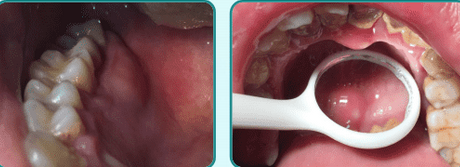

牙髓息肉的治疗方法,重点速览!